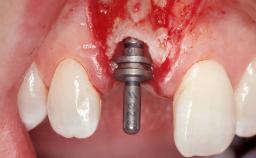

Immediate Placement of an Implant in a Maxillary Left Central Incisor Site

| Placement Protocol | Immediate implant placement |

| Tooth Site | Maxillary incisor or canine |

| Socket Morphology | Single-root socket |

| Socket Integrity | Damage to one or more bone walls |

| Bone Volume | Damage to one or more socket walls |